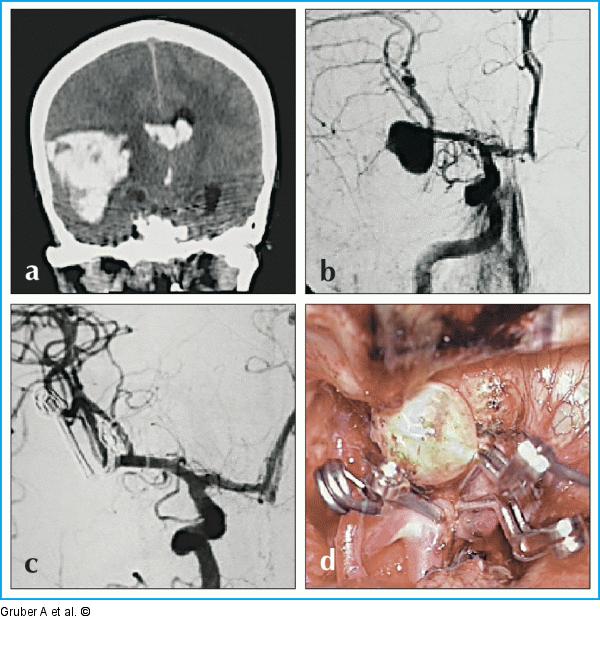

Abbildung 9a-d: Mikrochirurgische Klippung Mikrochirurgische Klippung von schmalbasigem Mediabifurkationsaneurysma rechts in der Akutphase nach aneurysmatischer Subarachnoidalblutung und raumfordernder intrazerebraler Blutung rechts temporal. Radiologische (a) und klinische Zeichen der Herniation zwingen zur akuten Hämatomentleerung und chirurgischen Therapie des an sich embolisierbaren (b) Aneurysmas. Intraoperative DSA (c) und mikrochirurgische Inspektion (d) zeigen den Aneurysmaverschluß. |